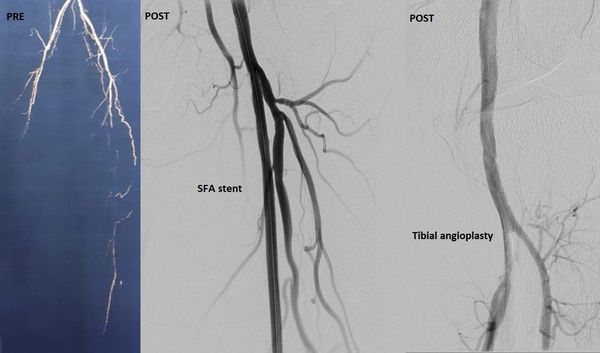

جراح أوعية دموية متخصص في علاج الوحمات الدموية للأطفال - انسداد الشرايين - قدم السكري والغرغرينا -علاج دوالي الساقين بالليزر

استشاري جراحة الأوعية الدموية و القسطرة التداخلية الطرفية